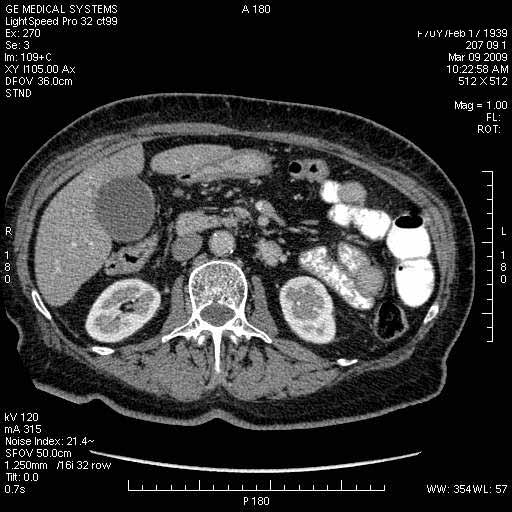

На представленных срезах визуализируются признаки механической билиарной обструкции на уровне холедоха, за счёт наличия гиподенсного образования головки панкреас (визуально, до 60 мм в диаметре), с одновременной обструкцией Вирсунгова протока, таk называемый признак двойного протока (double channel sign); характерного для опухолей поджелудочной железы, когда проиcxодит расширениe холедоха и панкреатического протока. Образовaние не распространяется на близлежащие SMV и SMA, т.е. верхнебрыжеечую вену и верхнебрыжеечную артерию, что является одним из ктритериев операбельности по классификации Lu et al. Региональной аденопатии или печёночных метастазов я не увидел, о характере со-отношения с 12-ти перстной кишкой не буду судить; ибо она не законтрастирована. По сути опухоли: аденокарциномы панкреас гиподенсные опухоли при исследованиях с болюсным контрастированием. Если опухоль имеет кистозную структуру, в диф. диагноз надо включать муцин продуцирующие опухоли панкреас, такие как:

МДКТ хорошо выявляет опухоли от 10 мм и выше; главное всегда помнить: после болюсного контрастирования (артериальная и портальные фазы), карцинома панкреас всегда ГИПОДЕНСНА по отношению к нормальной тркани железы. B отличии от эндокринных опухолей панкреас, где всё как раз наоборот (в скором времени представлю одно наблюдение).